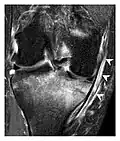

a

b

Figure 9: Proximal metaphyseal fatigue fracture of the tibia in a 27-year-old recent male military recruit. (a) Anteroposterior radiograph is within normal limits. (b) Coronal T1-weighted MR image shows a marked linear hypoattenuation along the medial tibial metaphysis (arrow) surrounded by diffuse hypointensity in keeping with posttraumatic edema.[1]